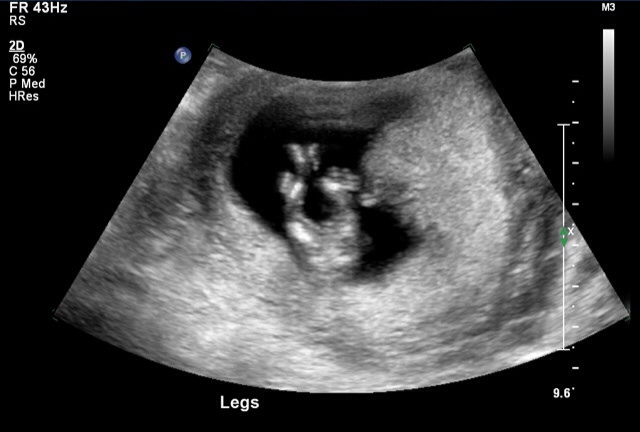

13.4 week NT scan – between leg shot – boy?? :) Crazy Infertile: 12 Week NT Scan